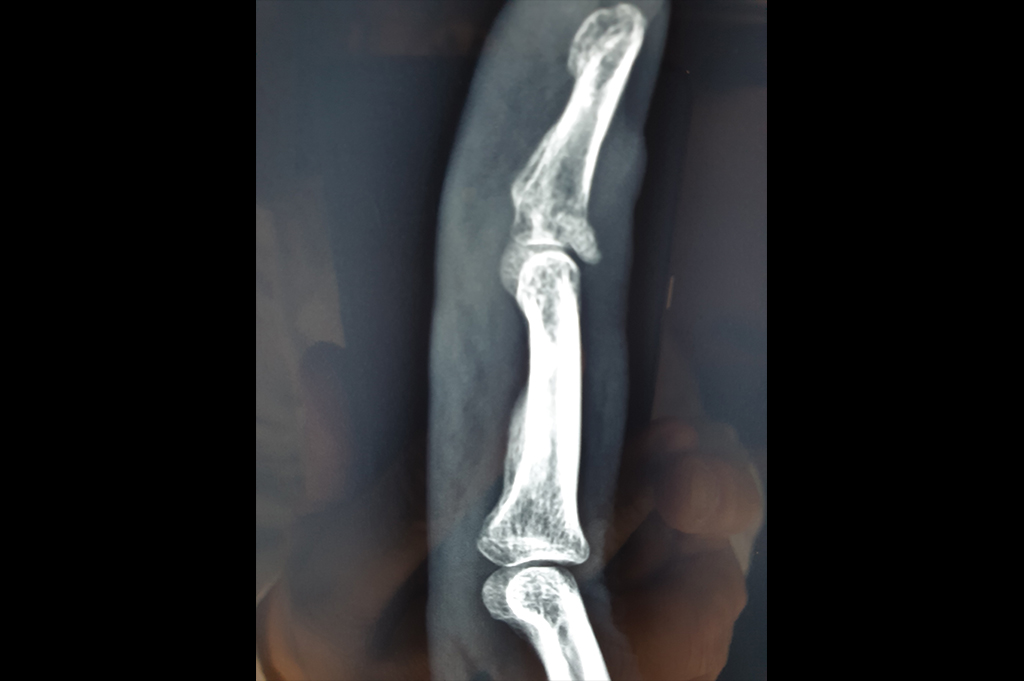

Mallet Finger